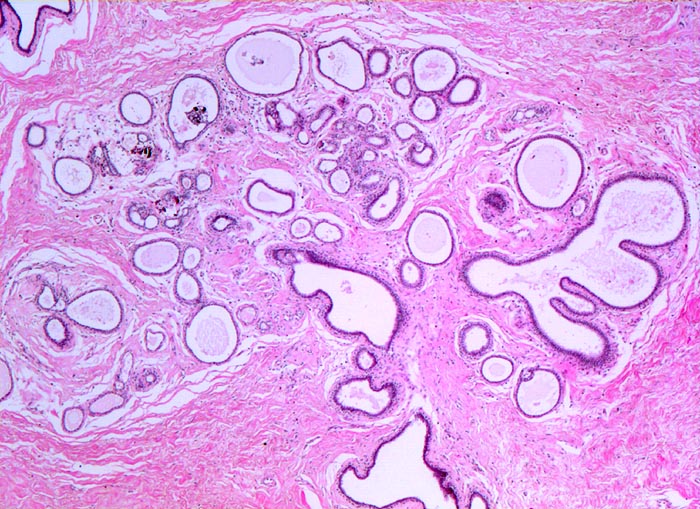

Makroskopisch bildet das mastopathisch veränderte Parenchym weisse kompakte fibröse Areale mit Einschluss von Zysten, welche oftmals eingedicktes Sekret enthalten. Neben einer Stromafibrose und zystisch ausgeweiteten Gängen mit Sekretretention findet sich oft eine unterschiedlich ausgeprägte intraduktale Proliferation von luminalen und basalen Epithelzellen. Nicht selten liegen als Begleitbefund kleine Fibroadenome, eine sklerosierende Adenose oder Gänge mit apokriner Metaplasie vor. Oftmals finden sich auch intraduktale Mikroverkalkungen. Die duktale Hyperplasie ist im Gegensatz zur atypischen Hyperplasie und zum Carcinoma in situ charakterisiert durch eine bunte, ungeordnete Proliferation ungleich grosser polygonaler bis spindeliger Zellen mit Ausbildung von schlitzförmigen Hohlräumen oder dünnen epithelialen Brücken. Die euchromatischen Kerne variieren in Grösse, Form und Lagerung. Bei paralleler Lagerung der Kerne entsteht der Eindruck eines Strömens und Fliessens der Zellen. Das duktale Carcinoma in situ ist von gutartigen intraduktalen Epithelproliferationen abzugrenzen aufgrund seiner Monomorphie (> 5185), Hyperchromasie der Zellkerne und starrer geometrischer Muster (runde scharf begrenzte wie ausgestanzte Lumina (> 5184), breite Brücken und Bögen, Mikropapillen). Eine intraduktale Epithelproliferation mit Atypie wird dann diagnostiziert, wenn nur ein Teil der Gänge oder Läppchen die typischen Veränderungen eines Carcinoma in situ zeigt. Die Abgrenzung der atypischen Hyperplasie von der Hyperplasie ohne Atypie erfolgt aufgrund qualitativer Merkmale und die Abgrenzung der Hyperplasie mit Atypie vom Carcinoma in situ aufgrund quantitativer Merkmale.

• Ausgeprägte Fibrose und zystisch erweiterte Gangstrukturen in organoider Anordnung.

• In der Mitte rechts einige Gänge mit gewöhnlicher intraduktaler Epithelhyperplasie ohne Atypie: Polymorphe, sich überlagernde spindelige Zellen. Fliessende Anordnung der Zellen. Schlitzförmige und irregulär geformte Lumina.

• Im Zentrum des Präparates stark erweiterte Gänge mit intraduktalen peripheren Papillomen.

• Alle Drüsen zeigen eine erhaltene äussere abgeflachte Myoepithelschicht mit hellem Zytoplasma.